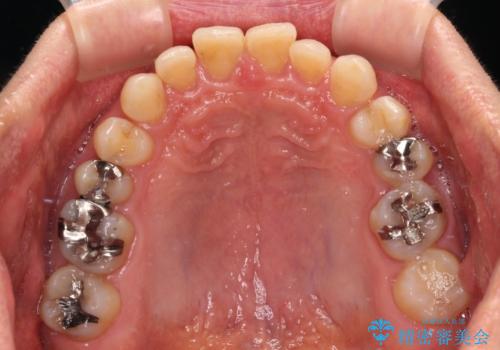

- 前歯のデコボコと隙間の空いた歯列を気にして来院された患者様です。

下顎前歯が隠れるほどのディープバイトにより、強い咬合力と突き上げで上顎歯列に隙間が空いている状態でした。

手前に傾斜している奥歯をワイヤー装置で立ち上がらせ、咬み合わせの高さを挙上することで突き上げを解消し、空隙歯列を改善していくこととしました。

ディープバイトが改善され、睡眠時の食いしばりも緩和され、顎への負担が軽減されました。